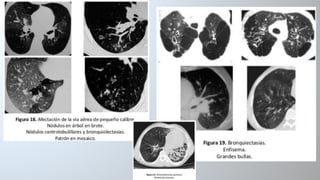

TC de tórax

signos directos

• Dilatación bronquial: presencia de un diámetro

bronquial interno mayor que el de la arteria

bronquial adyacente (índice broncoarterial >1).

• Bronquio dilatado forma un anillo y la arteria

acompañante, el sello.

• Imágenes aéreas con pared definida o lesiones

quísticas, con o sin nivel hidroaéreo.

• Bronquios dilatados: Signo de “raíl de tranvía”

• Ausencia de reducción del calibre bronquial desde

la división discotómica.

signos indirectos

• Impactos mucoides: bronquio dilatado y repleto de moco. Pueden

aparecer como opacidades lobuladas, en dedo de guante ramificadas

(V o Y) o redondeadas.

Engrosamiento pared bronquial (>50% del diámetro de la arteria

adyacente).